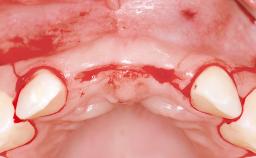

A 30-year-old woman was referred by her general dentist for evaluation of an esthetic complication related to previous implant treatment for congenitally missing maxillary lateral incisors. The patient’s chief complaint was the inadequate esthetic appearance of her smile. The case demonstrates the use of a combined approach to achieve optimal results. Two different flap designs - a tunnel technique and a coronally advanced flap - are employed based on the surgical objectives for the affected site.

Soft Tissue Grafting Yes